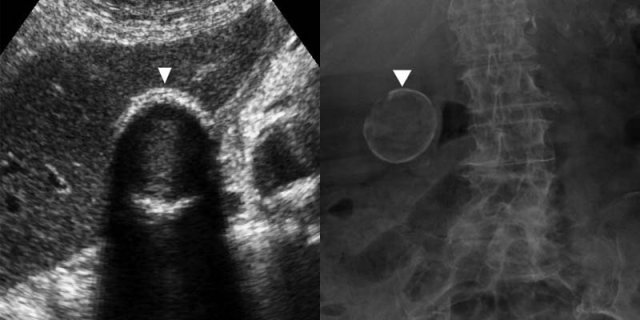

On the left images of a 49-year-old woman with chronic cholecystitis.

This patient had fasted overnight, so the wall-thickening does not represent physiologic contraction.

Correlation of these findings with her clinical history of recurrent colic-like right upper quadrant pain, due to transient gallbladder obstruction, is essential for the diagnosis.